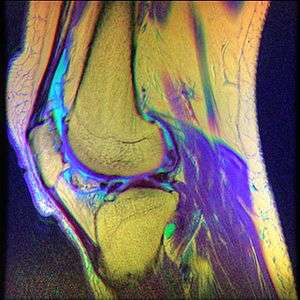

Chondromalacia patellae (also known as CMP) is inflammation of the underside of the patella and softening of the cartilage.

While the term chondromalacia sometimes refers to abnormal-appearing cartilage anywhere in the body,[6] it most commonly denotes irritation of the underside of the kneecap (or "patella"). The patella's posterior surface is covered with a layer of smooth cartilage, which the base of the femur normally glides effortlessly against when the knee is bent. However, in some individuals the kneecap tends to rub against one side of the knee joint, irritating the cartilage and causing knee pain.[7]